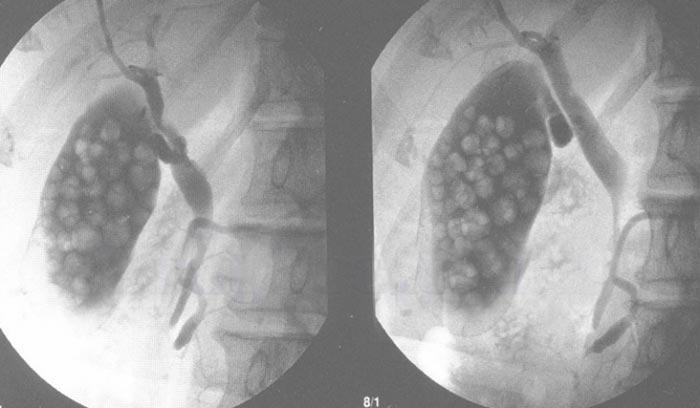

Обследование, с помощью которого изучают анатомию и физиологию билиарного тракта, моторику ЖП, степень проходимости желчевыводящих каналов, называют сцинтографией. Согласно методике, в организм больного внутривенно вводят радиоактивный изотоп. Препарат метаболизируется печёночными клетками и выделяется в билиарную систему. Сканирование выполняют с интервалом в 10–15 минут на протяжении 1–2 часов.

С помощью динамической сцинтографии отслеживают движение желчи из ЖП. В отличие от УЗИ, сцинтография не позволяет выявить конкременты в билиарном тракте. А у пациентов, которые перед исследованием принимали спиртные напитки, может проявиться ложно-положительный результат.

Как правило, во время сцинтографии оценивают состояние желчного и печени.

Сцинтиграфия ЖП

Рентгенологический метод позволяет дать оценку физиологии и анатомии билиарного тракта, установить моторику желчного пузыря, проверить проходимость каналов. Принцип метода заключается в том, что в организм вводят радиоактивный изотоп, который метаболизируется печенью и выделяется в билиарную систему. Сканирование проводят неоднократно с интервалом в 10-15 минут в течение 1-2 часов.

Способ позволяет отследить движение желчи из пузыря, но не используется отдельно. В отличие от УЗИ методика не позволяет обнаружить конкременты в желчном пузыре. К такой диагностике надо готовиться, минимум за 10 дней из рациона убирают весь алкоголь, иначе результаты будут ложными.